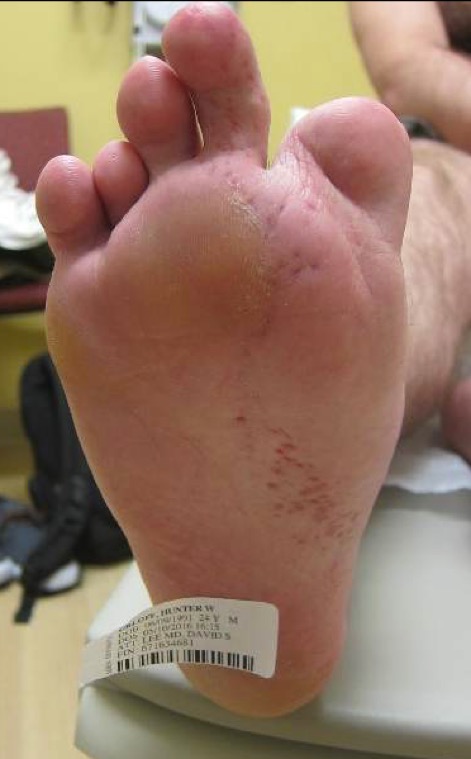

24-year-old German male with history of multiple basal cell carcinomas (BCC) presented to USC. At this visit, two suspicious lesions from right nasal bridge and right dorsal fifth finger were biopsied and came back as BCC. His physical exam was also significant for extensive atrophic erythematous patches on right nasal sidewall, right hand, and right lower extremity. He had multiple surgeries on his right leg due to premature closure of the growth plate and polydactyly. He was previously told that he may have Goltz syndrome but no genetic testing was done. Subsequently, he developed 2 more BCCs in the base and lateral aspects of dorsal right fifth digit within the erythematous atrophic patches.

Basal Cell Carcinoma, Coloboma Polydactyly of Right foot, Premature closure of Right lower extremity

Basal Cell Carcinoma along atrophic erythematous blashkoid patches